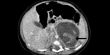

أظهر تصوير جسم جنين المولودة بالموجات فوق الصوتية الذي أجري قبل ولادتها وجود انتفاخ غريب في منطقة بطنها. وفي النتيجة أجرى الأطباء عملية لها بعد ثلاثة أسابيع من الولادة، حيث وجدوا جنينين بين كبدها وكليتها بوزن 9.3 غرام و14.2 غرام، ما يوافق فترتي الحمل لمدة سبعة وتسعة أسابيع.